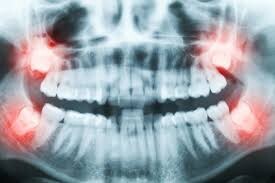

Wisdom teeth are your third set of molars set far back in the mouth. They develop when you’re between the ages of 17 and 25. When the wisdom teeth cause pain and/or are impacted, it’s recommended to get them removed. Let’s look at how these teeth came into being in the first place and what will happen if you need them removed.

Even if the wisdom tooth causes no symptoms, your dentist may recommend removal to prevent further damage or decay. The wisdom tooth will need to be extracted if it is impacted. An impacted wisdom tooth means the tooth is growing in at an odd angle that could affect nearby teeth or that the tooth sits along or within the jawbone.